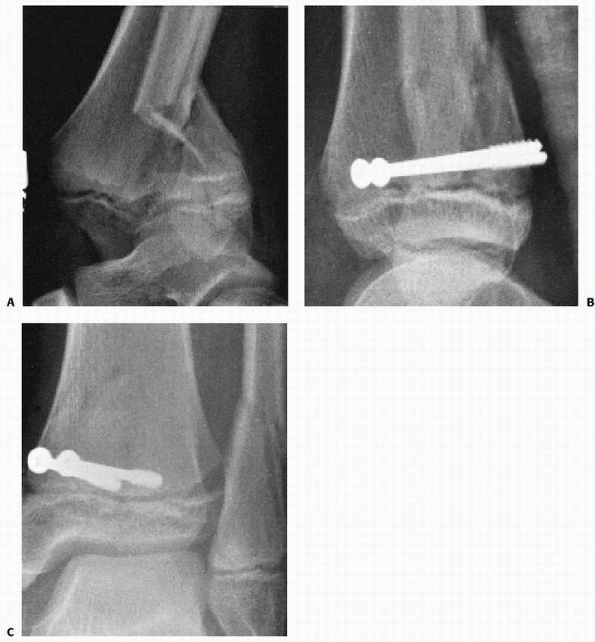

![]() |

FIGURE 26-35 A.

Severe ankle injury sustained by an 8-year-old involved in a car accident. The anteroposterior view in the splint does not clearly show the Salter-Harris type IV fracture of the tibia. The dome of the talus appears abnormal. B. CT scan shows the displaced Salter-Harris type IV fracture of the medial malleolus and a severe displaced intra-articular fracture of the body of the talus. C,D. Open reduction of both fractures was performed, and Herbert screws were used for internal fixation. (Courtesy of Armen Kelikian, MD.) |

displaced intra-articular fractures require as anatomic a reduction as

possible. Studies in children confirming the importance of articular

reduction to within 2 mm are lacking,166

although most recommend articular reduction in displaced fractures

involving the articular surface. Failure to obtain anatomic reduction

may result in articular incongruity and posttraumatic arthritis, which

often becomes symptomatic 5 to 8 years after skeletal maturity.34

The risk of growth arrest has also been linked to the adequacy of

reduction, although the literature is still unclear if anatomic

reduction reduces the risk of physeal arrest (Fig. 26-36).100